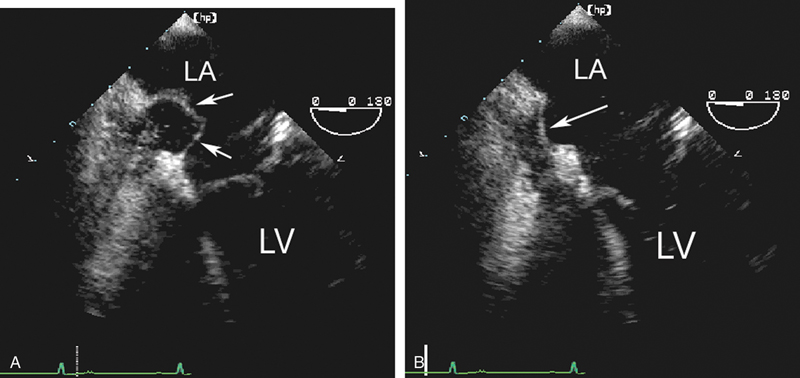

فحوصات تشخيصية لبعض امراض القلب والشرايين التاجية